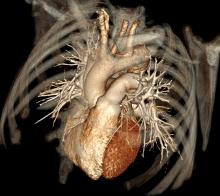

We are at an inflection point with many aspects of medicine, not the least of which concerns choosing the correct tool to discover and manage coronary artery disease. The American landscape of clinical and imaging service providers is going through a major reshuffle. Coronary computed tomography angiography (CTA) is growing in utilization, taking its place as an established modality with AHA-, ACC- and ACR society-derived appropriate use standards. However, this growth in CT utilization and the resultant growth in per capita radiation exposure have elevated a very public debate about the risk of causing cancer versus the value of its information content.